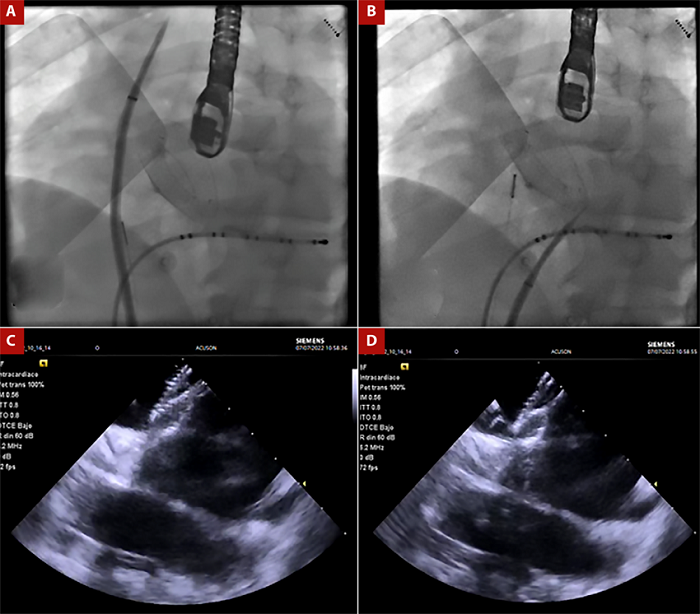

Paciente varón de 49 años, con antecedente de cierre de una comunicación interatrial tipo ostium secundum el año 2017, con un dispositivo oclusor del septum interatrial Amplatzer (Nit occlud N° 26). Al examen físico sin hallazgos relevantes. El paciente cursó con palpitaciones taquicárdicas asociadas a registro electrocardiográfico de fibrilación auricular paroxística y fluter atrial típico, siendo muy sintomático y refractario a terapia antiarrítmica, incluso presentó efectos adversos asociado a amiodarona como el hipertiroidismo. Adicionalmente, tuvo un intento frustro de ablación de FA por punción transeptal fallida guiada por ecocardiograma transesofágico en el 2019. Por tal motivo se realizaron estudios anatómicos previos al procedimiento cuyos hallazgos se describen en la Figura 1. Realizamos la ablación de fibrilación auricular con radiofrecuencia empleando el sistema de mapeo 3D Carto V7 (Biosense - Webster, Diamond Bar, California), mediante abordaje transeptal guiado por EIC, por lo que posicionamos la sonda de EIC Acunav ® en la aurícula derecha para visualizar el septum interatrial. Luego pasamos el introductor largo SL1 (Swartch Left, Abbot) posicionándolo en vena cava superior; posteriormente avanzamos la aguja de punción transeptal (BRK, St. Jude) (Figura 2). Inicialmente se guio la punción transeptal por fluoroscopia observando doble salto y ubicándonos en la parte caudal y anterior del Amplatzer; después, guiados por la EIC alcanzamos a evidenciar una imagen de «tienda de campaña» sobre el septum interatrial (SIA) remanente, y observamos en tiempo real el avance de la aguja sobre el introductor largo y el septum interatrial alcanzando la aurícula izquierda.

Figura 2 A. Vista fluoroscópica en proyección oblicua anterior izquierda donde se observa el introductor largo con la aguja de punción transeptal ubicados en la vena cava superior B. Presencia de introductor largo y la aguja transeptal a nivel del borde posteroinferior del dispositivo oclusor en el septum interauricular remanente. C. Imagen de ecografía intracardiaca que evidencia septum interauricular remanente en región posteroinferior y dispositivo oclusor. D Presencia de imagen en «tienda de campaña» en septum interauricular remanente cuando la aguja está a punto de atravesar hacia la aurícula izquierda.